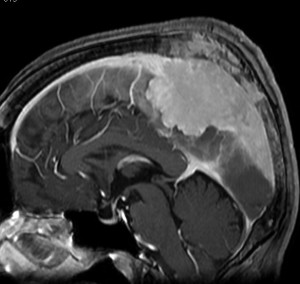

上矢状洞髄膜腫 superior sagittal sinus meningioma

上矢状洞を埋め尽くすように増大して,頭蓋骨浸潤が著しい髄膜腫ですが,ごく軽度の右足脱力以外に何の症状もありません。上矢状洞はゆっくり閉塞すれば,このような頭頂部から後頭部にわたる広範閉塞でも,静脈還流に障害がない場合が多いといえます。大脳の前半部の血流は前頭葉表面の皮質静脈から海綿静脈洞に側副路を形成しています。頭蓋内圧亢進所見もなく,これらはこの髄膜腫がゆっくり増大したということを示唆しています。

手術直後の画像です。全部いっぺんに摘出するのは無理なので,まず前から80%くらいの腫瘍を摘出しました。肥厚した骨はチタンプレートで置き換えてあります。後頭部の上矢状洞内と大脳鎌に少し残りましたが,この6ヶ月後に2回目の開頭術をして全摘出しました。結果的にこの例では,上矢状洞を冠状縫合のあたりから,静脈洞交会まで壁ごと全部摘出しましたが,脳浮腫も何も生じませんでした。腫瘍の両側にある皮質静脈 cortical veinsを損傷しないことが肝要です。

右の病理像は,頭蓋骨浸潤している部分 ですが,骨破壊は良性髄膜腫に特徴的な骨内浸潤像です。この骨浸潤像は悪性像とはいえません。MIB-1は高いところで8%、低いところで3%程度です。